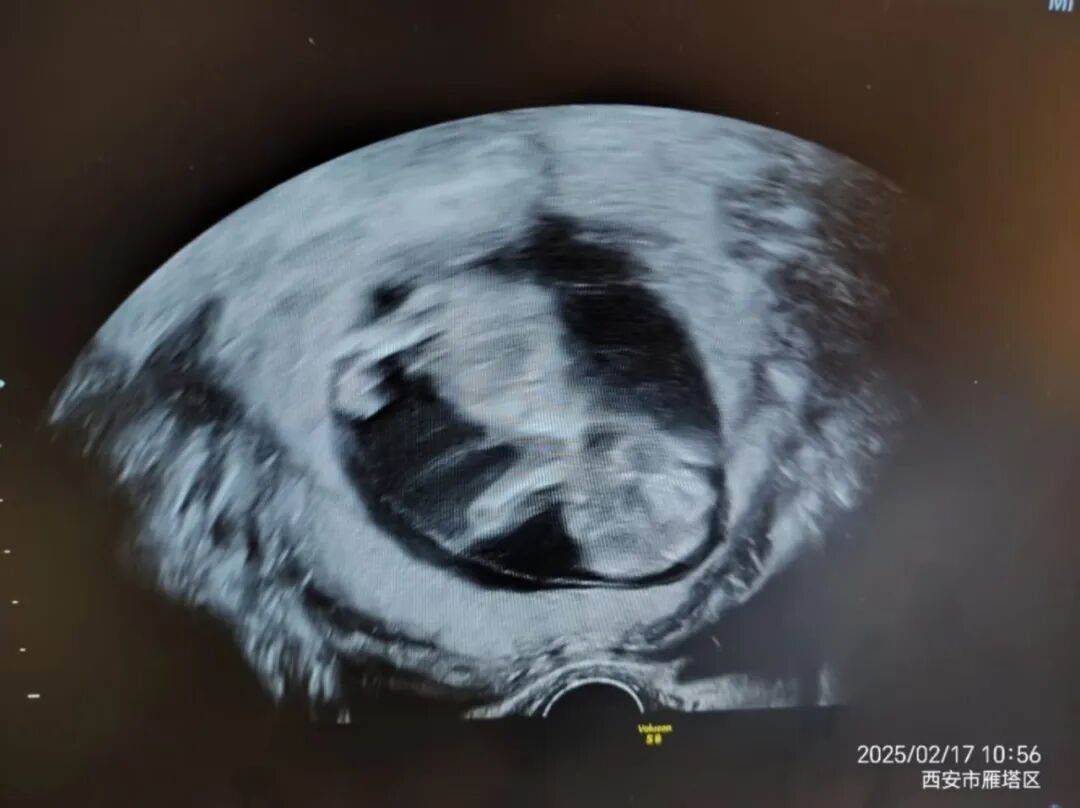

患者小莉合并患有子宫腺肌症,结缔组织病,易栓症等多种免疫疾病,高龄首孕,AMH值0.38,反复流产。在外院就诊保胎的十年间反复妊娠失败信心尽失,曹浩哲医生一再鼓励并坚持认为她还有希望拥有自己的宝宝。经曹医生精心诊治,积攒多个胚胎一次移植成功受孕,现已怀孕19周从取卵到移植,到保胎的整个过程,曹医生针对小莉病情的复杂和特殊性,不拘泥于传统模式与治疗方案,一人一方案精准问题,排查病情。尤其保胎过程中,几次险象环生,均得益于曹医生第一时间准确的诊断并即时有效处理。